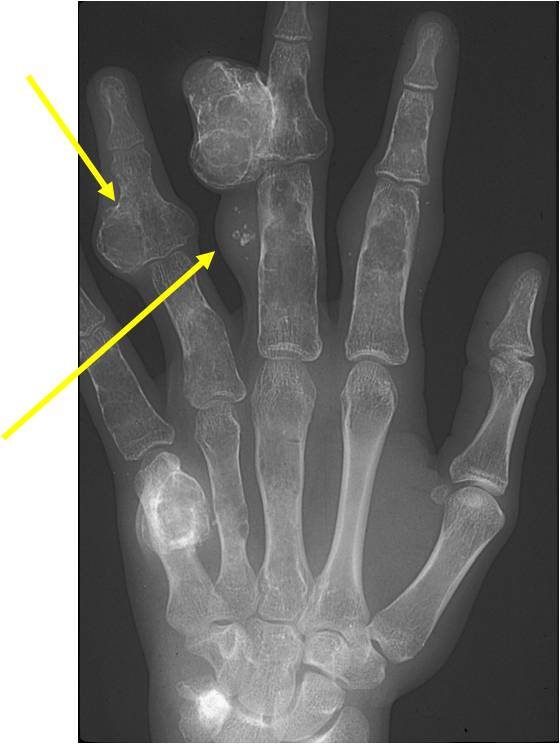

Enchondromatosis

- (Multiple Enchondromas/Ollier Disease

- Enchondromatosis is a rare disorder that is not hereditary in which the patient is afflicted with multiple intraosseous cartilaginous tumors or enchondromas.

- Usually affects the extremities

- Variable severity

- May be predominantly unilateral or affect a single extremity/limb

- Affected limb is often shortened and deformed and angulated

- May become stable at puberty

- Higher risk of malignant transformation to chondrosarcoma (5-50%) as opposed to an isolated enchondroma

- Marked skeletal deformity

Enchondromas in enchondromatosis may involve the metaphysis, diaphysis, epiphysis and articular cartilage